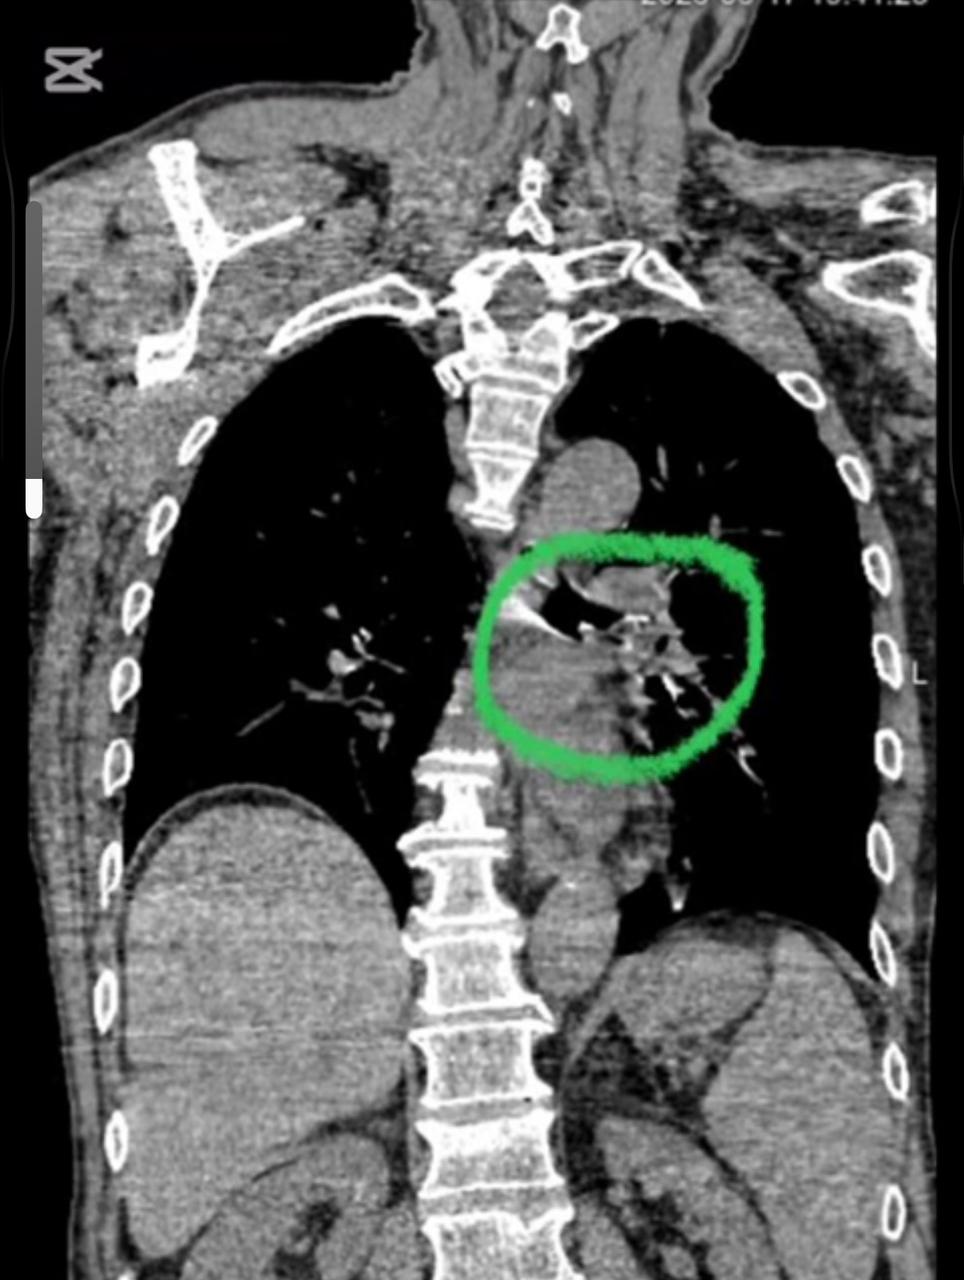

Науқастың сол жақ бас бронхында көлемі 2,0х1,5 см болатын алма бөлігі табылып, ол толықтай тыныс жолын бітеп қалған. Жағдайды едәуір күрделендірген қосымша аурулары да болды: 1995 жылы өткерген жедел ми қанайналым бұзылысының салдары, дизартрия, сол жақты гемипарез, сондай-ақ III дәрежелі артериялық гипертензия (ФК 4).

Конаев қалалық орталық ауруханасының ота бөлмесінде маман бейнебронхоскоп аппаратының көмегімен, интубациялық наркозбен бөгде затты сәтті алып тастады. Дәрігердің жедел әрі кәсіби іс-әрекетінің арқасында науқастың тыныс жолдары толық қалпына келтіріліп, өміріне төнген қатер мен ауыр асқынулардың алдын алынды.